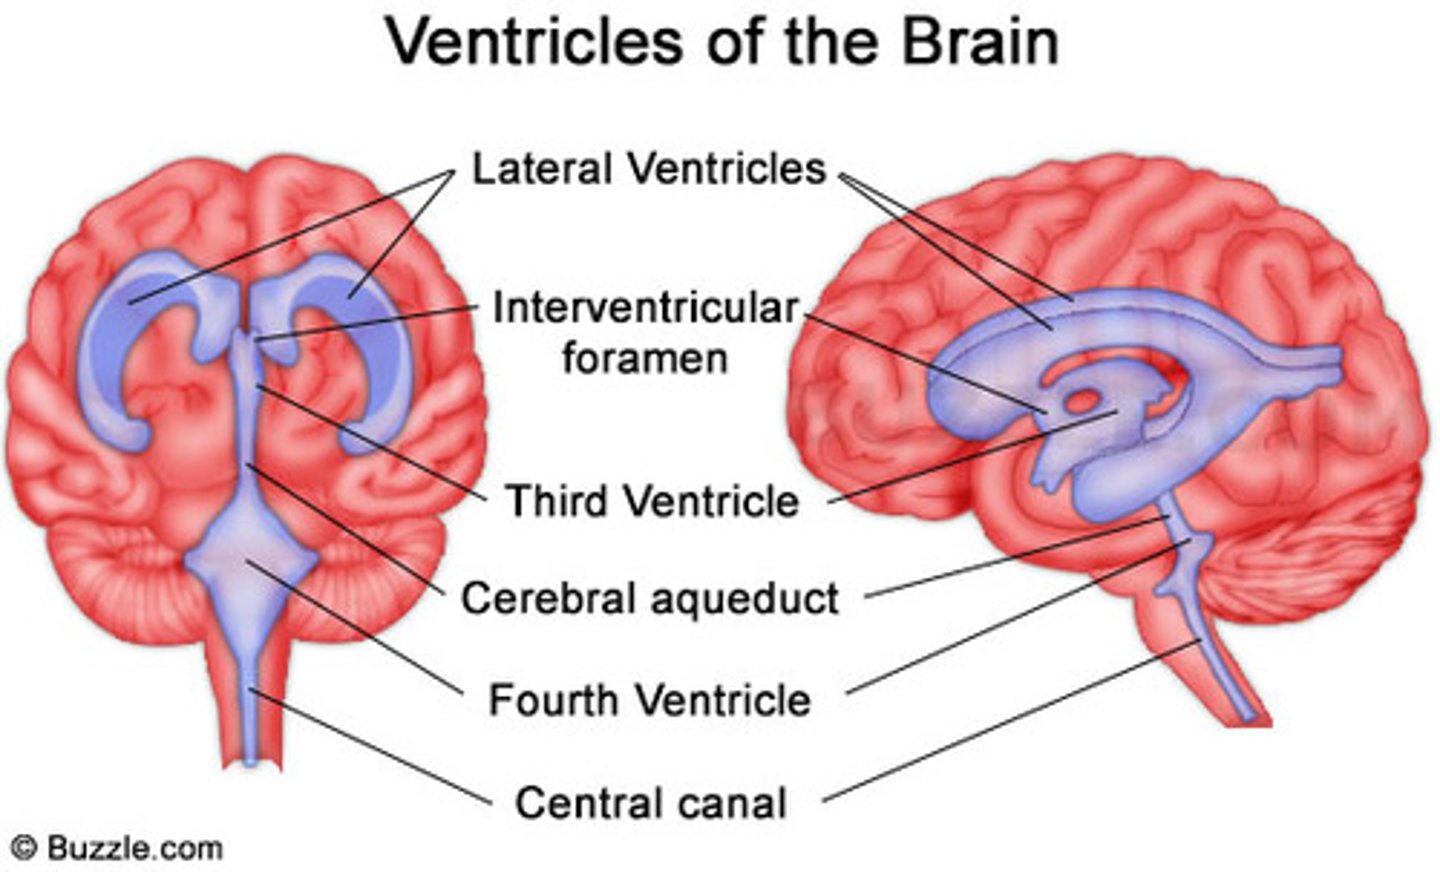

The opening of the neural tube become

Ventricles

4 Chambers within the brain,

Filled with Cerebrospinal Fluid,

Continuous with each other and with the central canal of the spinal cord

4 Chambers within the brain,

Filled with Cerebrospinal Fluid,

Continuous with each other and with the central canal of the spinal cord

Ventricles

1) Right & left lateral ventricles:

-Anterior, Posterior & inferior horns

2) 3rd Ventricle, Cerebral aqueduct, 4th ventricles

4) Apertures (Narrow openings) into subarachnoid space of spinal cord

Anterior Horns

Posterior Horns

Inferior Horns

3rd Ventricle

4th Ventricle